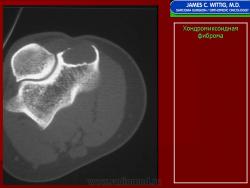

Рентгенологическое исследование показывает, что опухоль растет экзофитно в зоне метафиза и распространяется по направлению к эпифизу. Она имеет четкие и фестончатые очертания. На фоне характерных литических изменений изредка видны участки обызвествления. Наиболее агрессивный вид имеет хондромиксоидная фиброма, локализующаяся в позвонках. Здесь часто отмечается прорастание надкостницы. Макроскопически представляет собой четко отграниченную опухоль, имеющую дольчатое строение, плотную консистенцию, серовато-белый или синюшно-серый цвет. При прорастании новообразования через кортикальный слой надкостница сохраняется. В редких случаях наблюдается имплантация опухолевой ткани в окружающие мягкие ткани. Для лечения хондромиксоидной фибромы используется кюретаж. Рецидивы наблюдаются в 10—15 % случаев, обычно в течение первых 2 лет после операции, чаще всего у лиц моложе 15 лет.

Рентгенологическая картина. Хондромиксоидная фиброма длинных трубчатых костей в типичных случаях представлена метафизарным или метадиафизарным, эксцентричным, четко очерченным, овальным очагом разряжения костной ткани с истон чением и вздутием коркового слоя с одной стороны.

Рентгенологическое исследование показывает, что опухоль растет экзофитно в зоне метафиза и распространяется по направлению к эпифизу. Она имеет четкие и фестончатые очертания. На фоне характерных литических изменений изредка видны участки обызвествления. Наиболее агрессивный вид имеет хондромиксоидная фиброма, локализующаяся в позвонках. Здесь часто отмечается прорастание надкостницы. Макроскопически представляет собой четко отграниченную опухоль, имеющую дольчатое строение, плотную консистенцию, серовато-белый или синюшно-серый цвет. При прорастании новообразования через кортикальный слой надкостница сохраняется. В редких случаях наблюдается имплантация опухолевой ткани в окружающие мягкие ткани. Для лечения хондромиксоидной фибромы используется кюретаж. Рецидивы наблюдаются в 10—15 % случаев, обычно в течение первых 2 лет после операции, чаще всего у лиц моложе 15 лет.